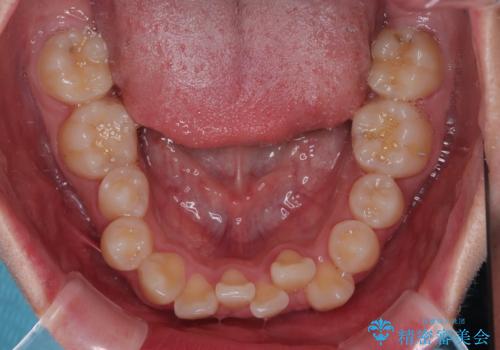

- クリアブラケット

- 1年6ヶ月

特に前歯のデコボコが顕著であり、上下左右第一小臼歯の4本を抜歯し、ワイヤー装置を使用して咬み合わせ高さを改善しながら、歯列を整えて行くこととしました。

移動が順調に進み、1年半の短期間で治療を終えることができました。

前方に突出した上顎前歯の傾斜も改善されました。